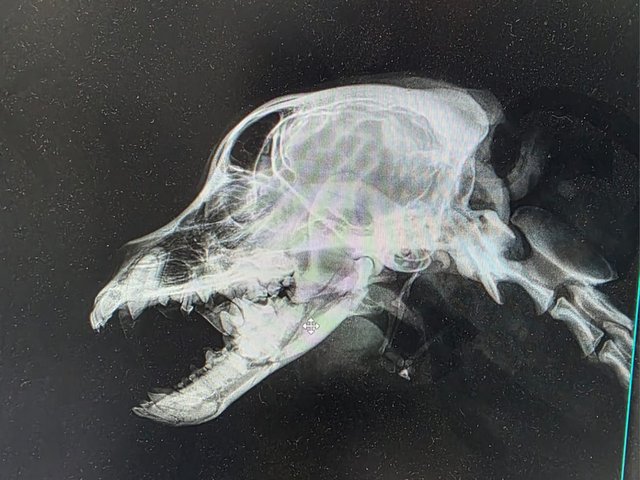

Röntgenbilder zeigten das Ausmaß der Zerstörung des Unterkiefers und den Bruch eines Beines.

Dieser Hund muss grausame Schmerzen haben, Zähne sind aus der Verankerung gerissen und sein Gesichtsschädel ist nicht mehr symmetrisch. Ein großes Stück des Unterkiefers ist komplett abgebrochen.

Es braucht sicher viel Geschick, um das wieder so zusammenzusetzen, dass der Hund später problemlos fressen kann.

Camush Kopf ist wieder symmetrisch, der Kiefer wird jetzt mit Platte und Verdrahtung zusammengehalten und ein paar Zähne fehlen jetzt.